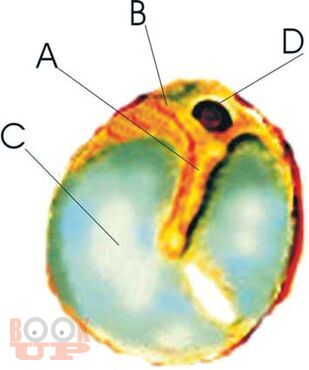

Данное руководство по Хроническому среднему отиту выполнено на кафедре послевузовского обучения специалистов по болезням уха, горла, носа Московской медицинской академии им. И.М.Сеченова. В результате последовательного анализа особенностей патофизиологического развития хронического воспалительного процесса в среднем ухе были выявлены три основных разновидности «порочного круга» его развития, которые и оказались основой хронического течения воспалительного процесса. Это позволило выявить патогенетические закономерности развития хронического среднего отита, разработать современные патогенетически обоснованные методы лечения для разных его форм и стадий. В результате, была составлена патофизиологически обоснованная классификация хронического среднего отита, которая значительно облегчает и ускоряет диагностику, помогает подбору наиболее результативного лечения и способствует выработке эффективных мер профилактики, как в условиях клиники, так и в поликлинических условиях. Новые методики защищены Российскими патентами. Данное руководство по Хроническому среднему отиту рекомендовано Учебно-методическим объединением по медицинскому и фармацевтическому образованию вузов России в качестве учебного пособия для практикующих врачей – специалистов по болезням уха, горла, носа.